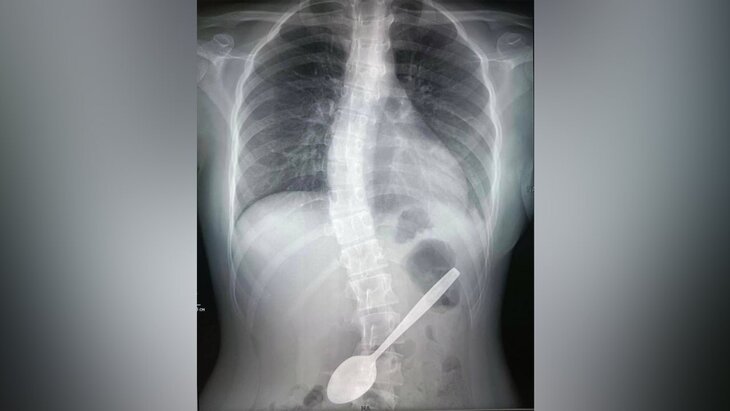

Подмосковные врачи извлекли из желудка девочки 15-сантиметровую ложку

Врачи Детского клинического центра имени Л. М. Рошаля спасли 14-летнюю девочку, которая случайно проглотила 15-сантиметровую ложку. Об этом сообщает пресс-служба подмосковного Минздрава.

По данным министерства, школьница пыталась с помощью ложки вытащить кусок яблока, застрявший у нее в горле. Врачи после сделанного рентгена, который подтвердил наличие инородного тела в желудке, решили провести ей операцию.

Воспользовавшись видеоскопом, медики обнаружили, что ложка упиралась тонкой частью в стенку желудка, а широкой – уходила в луковицу двенадцатиперстной кишки. Инородный предмет был извлечен с помощью эндоскопической петли и щипцов, а также хирургического зажима.

Операция продлилась примерно час и прошла успешно. В настоящее время девочка чувствует себя хорошо и выписана домой.

По словам врачей, если бы металлический предмет оставался в желудке на протяжении долгого времени, это могло спровоцировать серьезные осложнения, в том числе пролежни, перфорацию стенок желудка или непроходимость. Девочке, как указали врачи, повезло, так как ложка не нанесла вред ее здоровью.